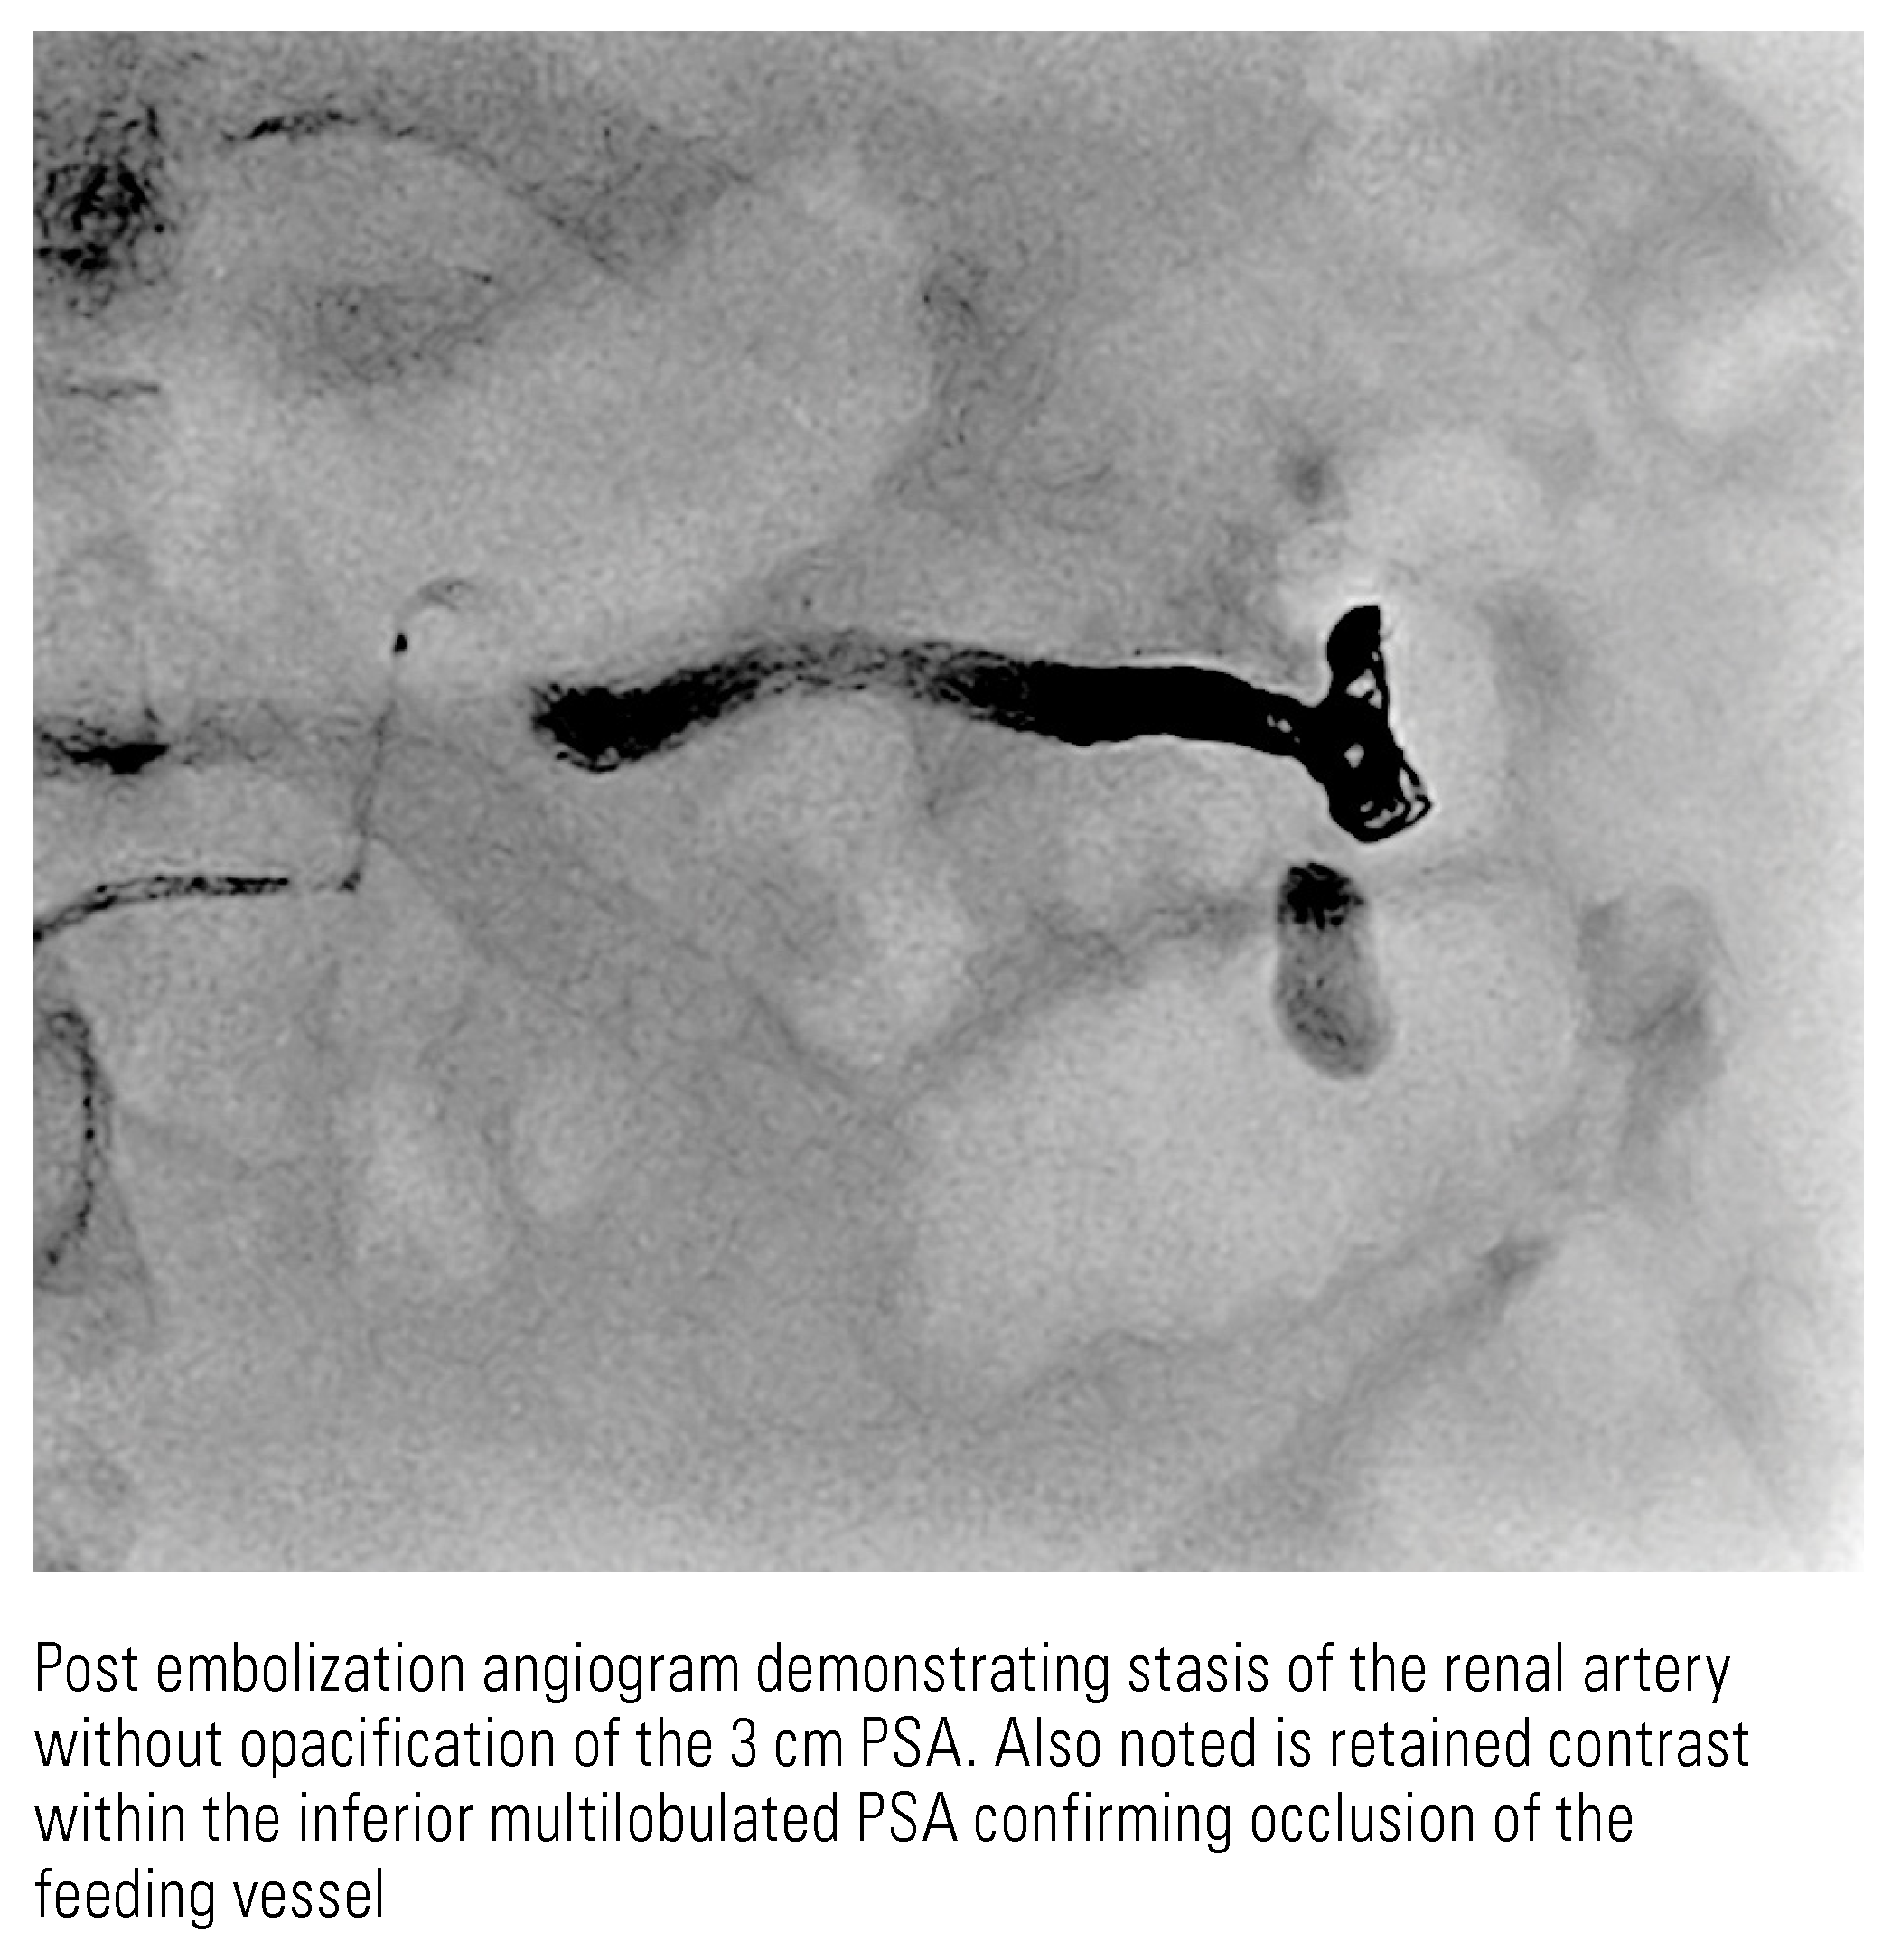

Renal Cell Carcinoma with Intratumoral Pseudoaneurysm